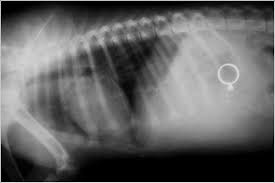

Les voleuses assurent avoir 12 et 13 ans. Doutant de leur âge "au vu de leur apparence" et étonnés de ne pas trouver de butin, les policiers du commissariat de la ville les emmènent à l'hôpital. Un examen osseux révèle qu'elles sont bien majeures et, surprise: les radios montrent qu'elles ont avalé les bijoux dérobés.

"On voit parfaitement une bague qui correspond en tous points à une bague volée", a décrit à l'AFP la même source.